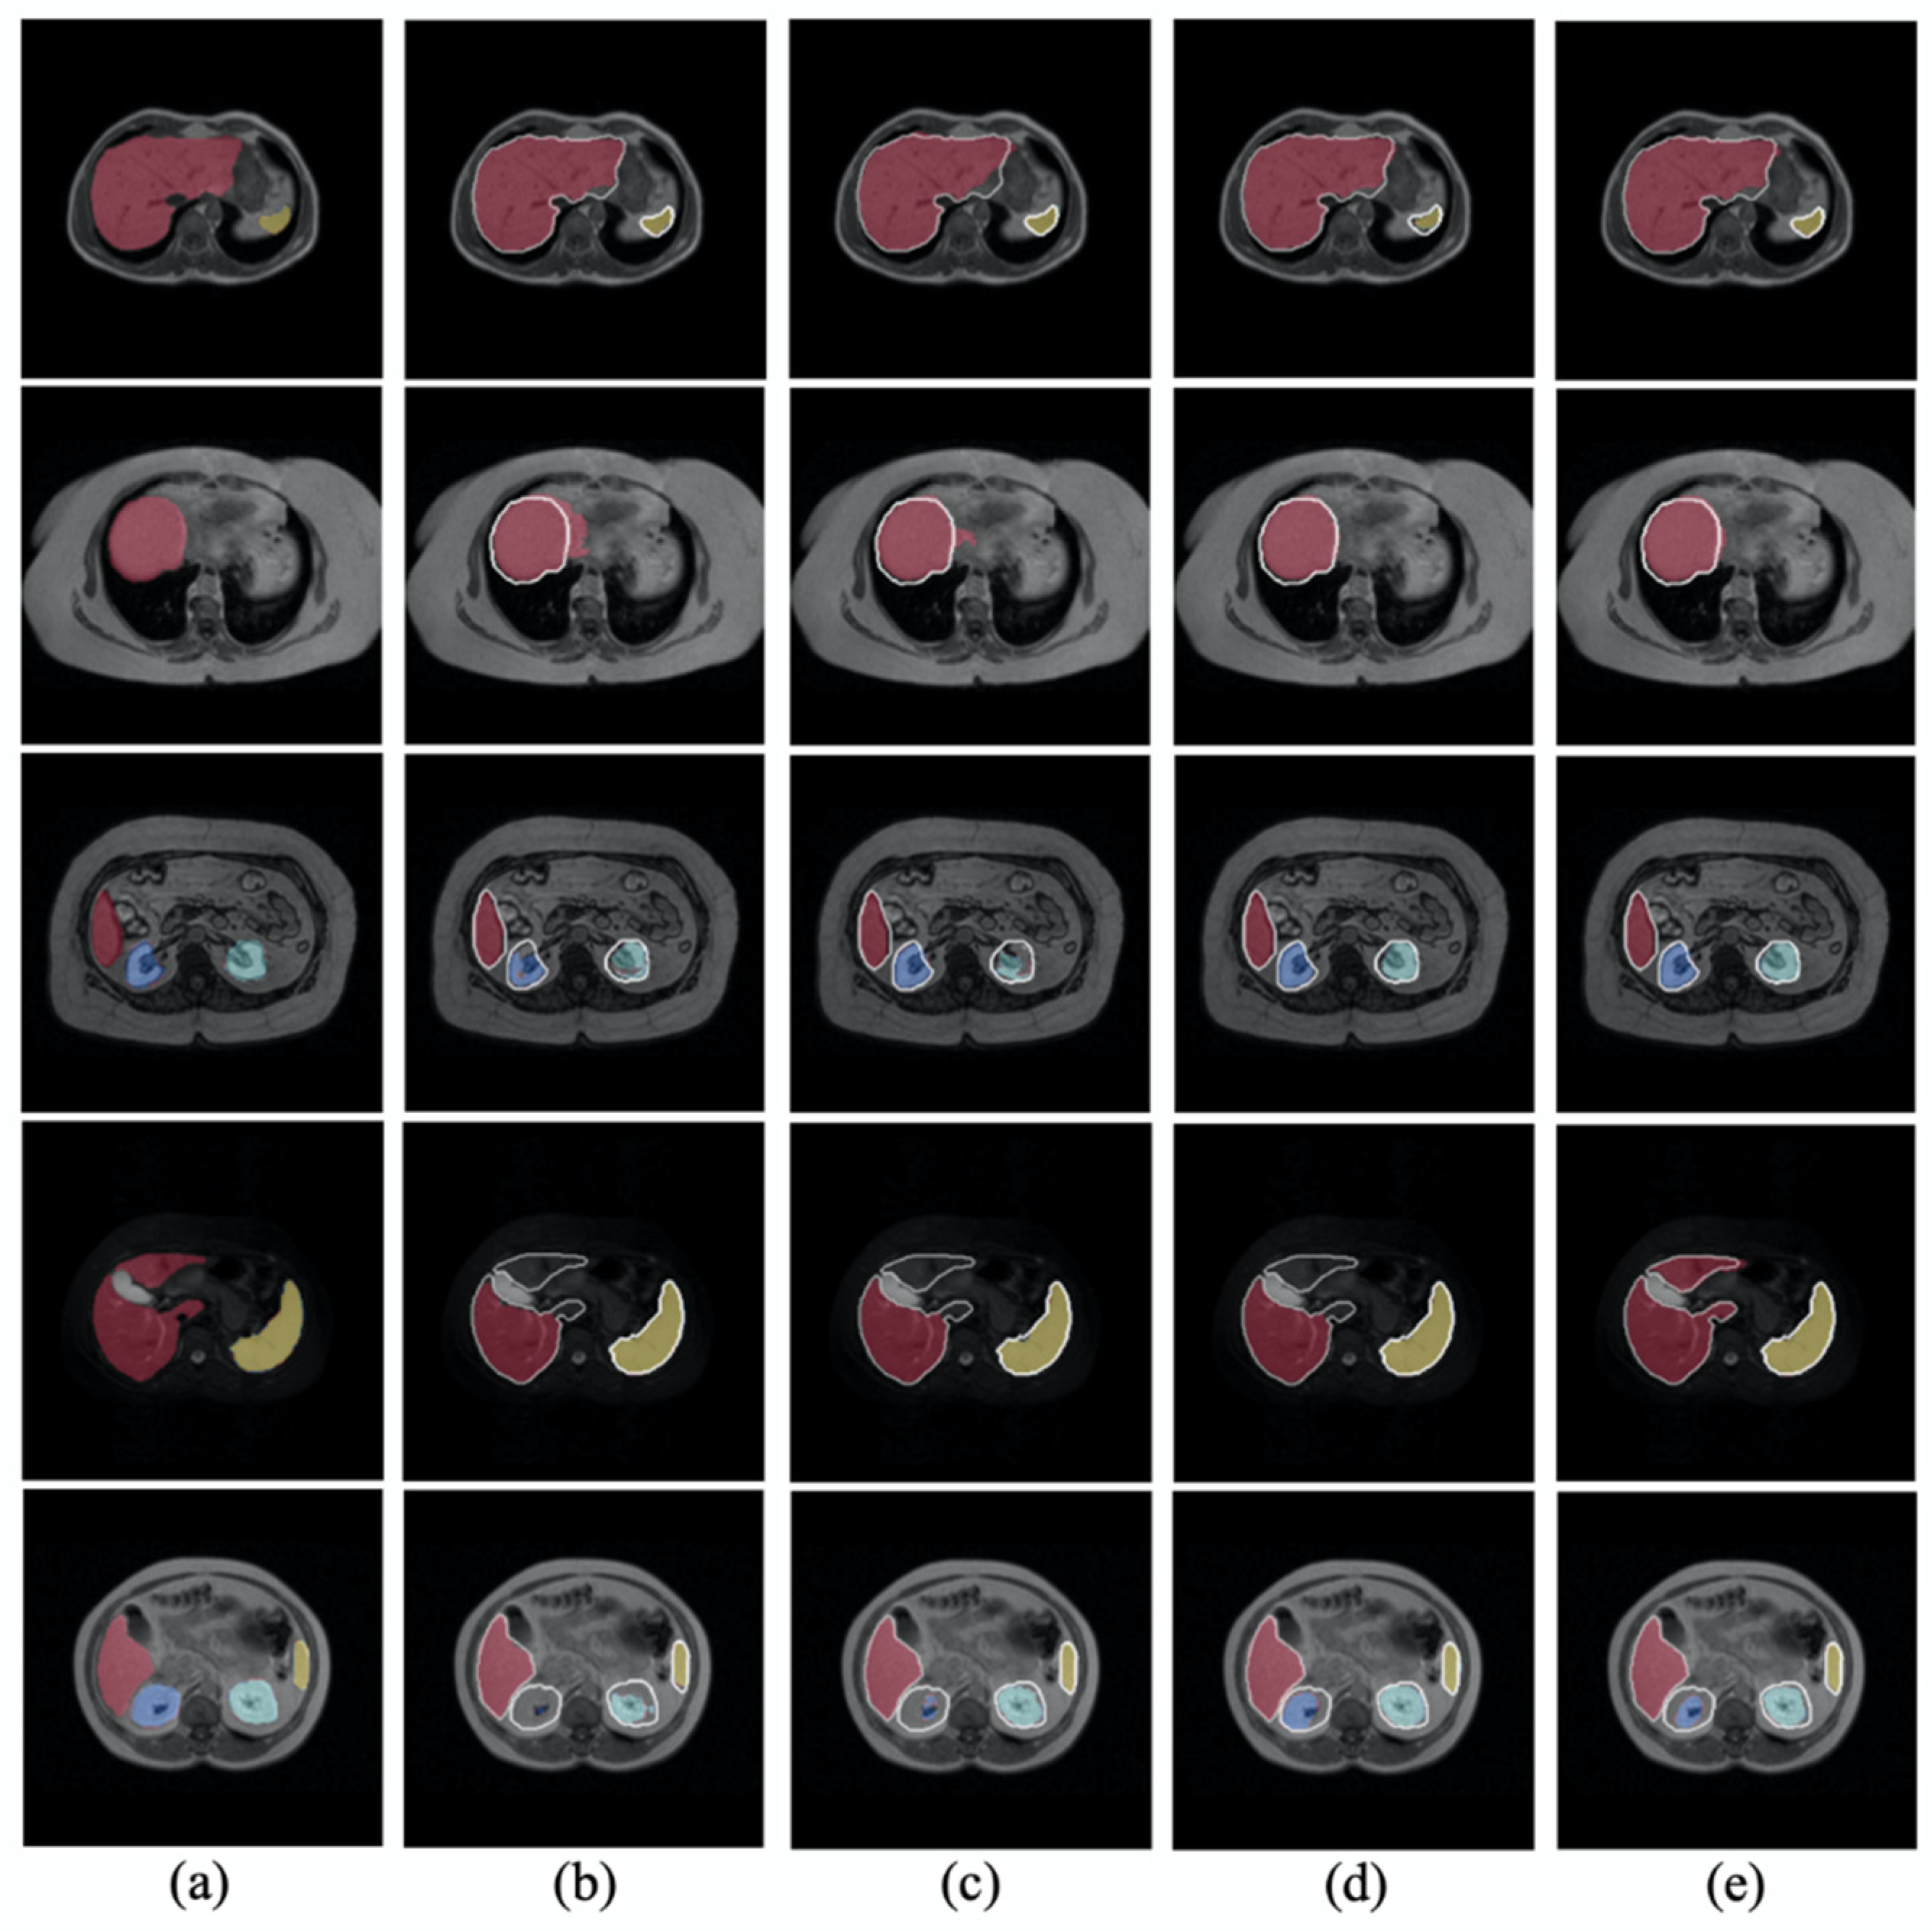

- We developed the contour-aware CNN and employed the voting strategy in our joint optimization framework.

- We validated our framework using two public datasets, abdomen MRI (CHAOS Challenge) and hippocampus MRI (the Medical Segmentation Decathlon), and could achieve comparable performance compared with other related methods.